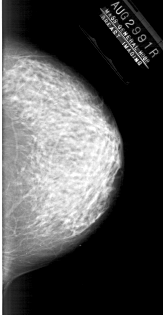

A_1878_1.RIGHT_CC

RIGHT_CC LINES 5971 PIXELS_PER_LINE 3091 BITS_PER_PIXEL 12 RESOLUTION 43.5 NON_OVERLAY